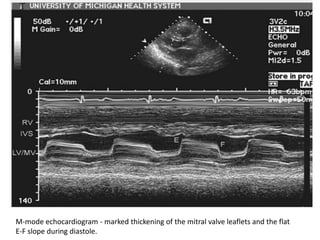

M-mode echocardiogram - marked thickening of the mitral valve leaflets and the flat

E-F slope during diastole.

Characteristic Changes • thickeningat the leaflet edges, fusion of the commissures, and chordal shortening and fusion. commissural fusion that results in doming of the leaflets in the long-axis view and in a decrease in the width of the mitral orifice in the short-axis view.

M-mode echocardiogram -marked thickening of the mitral valve leaflets and the flat E-F slope during diastole.

the diffuse thickeningof the mitral leaflets with the doming motion in diastole with diffuse thickening of the chordae